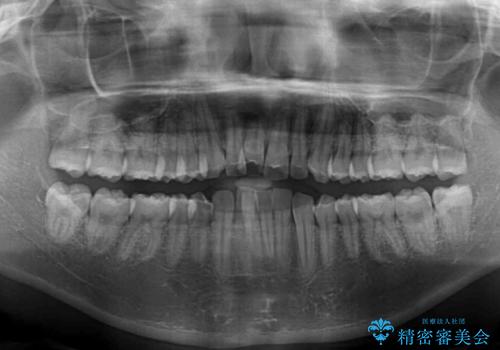

- 飛び出した前歯と全体的なデコボコを気にして来院された患者様です。

ワイヤーでもマウスピースでも治療可能でしたが、自己管理の重要なマウスピース矯正は自分には向かないとのことで、ワイヤー矯正で治療することとしました。

上下歯列全体を後方に移動させるため、親知らずは全て抜歯することにしました。